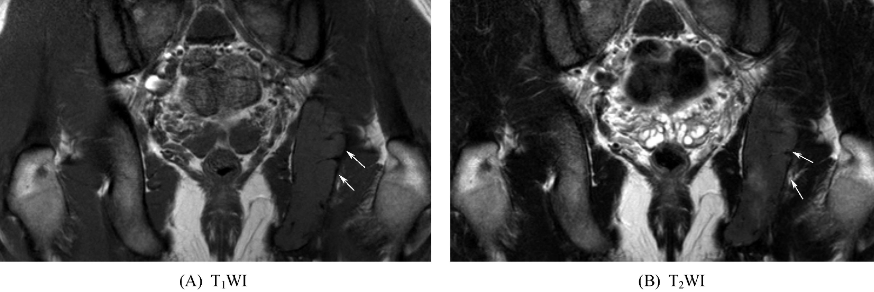

十二、嗜酸细胞肉芽肿

好发于颅骨,股骨次之,再次为脊柱、肋骨、骨盆等。表现为边界清楚,单发或多发圆形或卵圆形溶骨性破坏,内为长T1、长T2信号,周围无或轻度硬化,病变穿破骨皮质可形成软组织肿块。可伴有骨膜反应。增强扫描肿块可见强化。发生于颅骨者,多个病灶可融合,病变可跨越颅缝。发生于脊柱者可侵犯单个或多个椎体,椎体呈楔形或平板状(扁平椎),其横径及前后径均超出相邻椎体,相邻椎间隙多正常或稍增宽,椎旁可见局限性软组织肿块(图12)。在长骨,病变多累及干骺端和骨干,极少数累及骨骺。病变部位常有层状骨膜增生,且大多超越骨质破坏范围(图13)。

图12 脊柱嗜酸细胞肉芽肿胸6椎体呈平板状,其上下椎间隙正常,椎体周围可见软组织肿块。